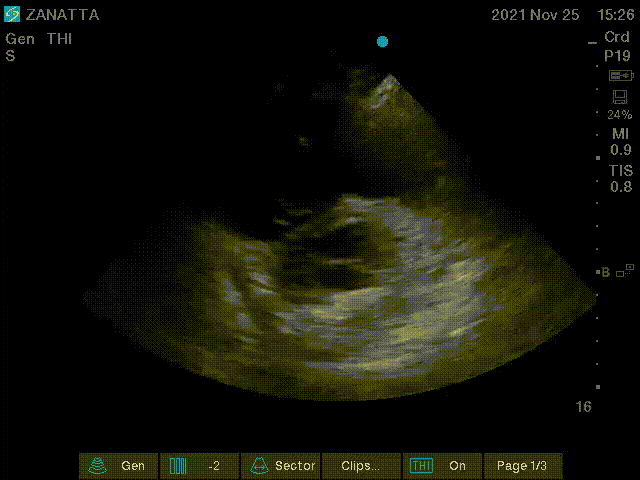

You move on to the parasternal long and short axis views.

Parasternal Long Axis